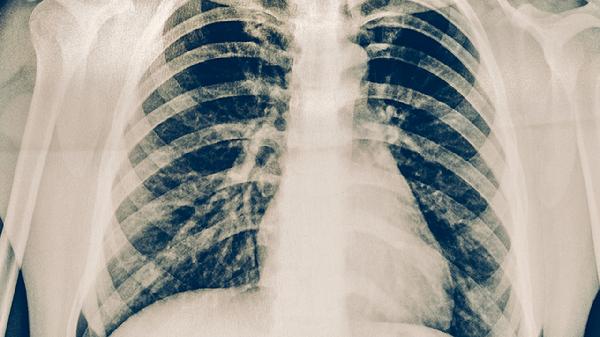

肋软骨炎主要通过体格检查和病史诊断,影像学检查多为排除其他疾病。肋间神经痛可能需要神经电生理检查、胸椎MRI等明确神经受压情况。